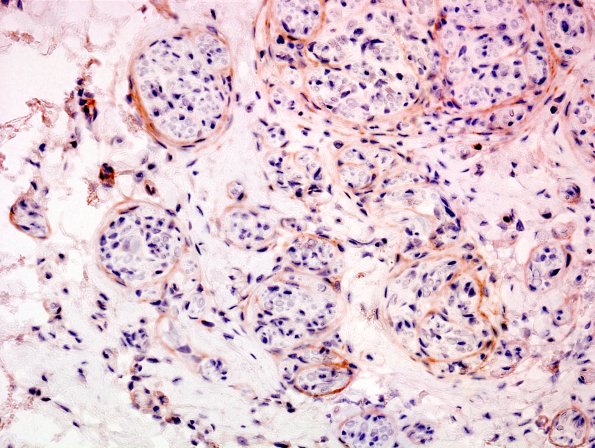

Immunohistochemical stains for EMA (epithelial membrane antigen) highlights the perineurium of the normal nerve and shows many mini-fascicles of the neuroma with a thin perineurium. (EMA IHC)